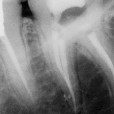

2/3 Postoperative x-ray Glide path with One G, Preflaring with One flare, Shaping with One curve in three waves up to the apex.

3/3 Postoperative x-ray Glide path with One G, Preflaring with One flare, Shaping with One curve in three waves up to the apex.